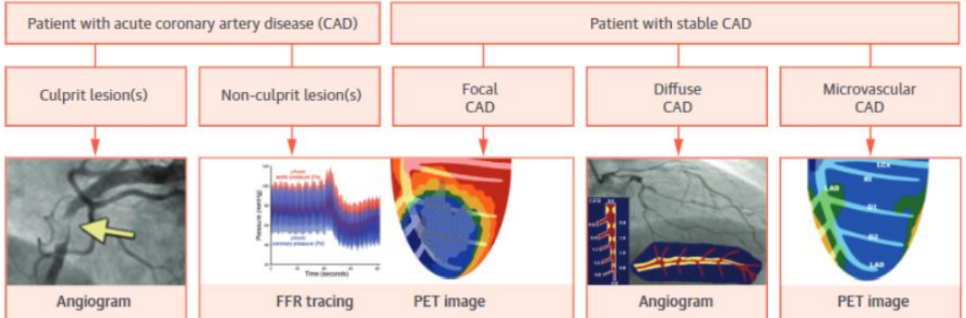

그 외에도 여러 가지 검사가 있지만, 고가의 검사이므로 정말 심장 혈관병인 분만 선택적으로 검사합니다.

그 외에도 많은 검사가 있지만 높은 검사이므로 심근경색이 있는 분만 필요에 따라 실시합니다.그래서 동맥 경화가 있으면 어떻게 해야 합니까?동맥 경화에 영향을 미치는 것에는 주로 어떤 것이 있는 것입니까.조절할 수 있는 것도 있고 조절할 수 없는 것도 있어요. 이런 부분은 현대의료과학의 도움을 받았으면 합니다.